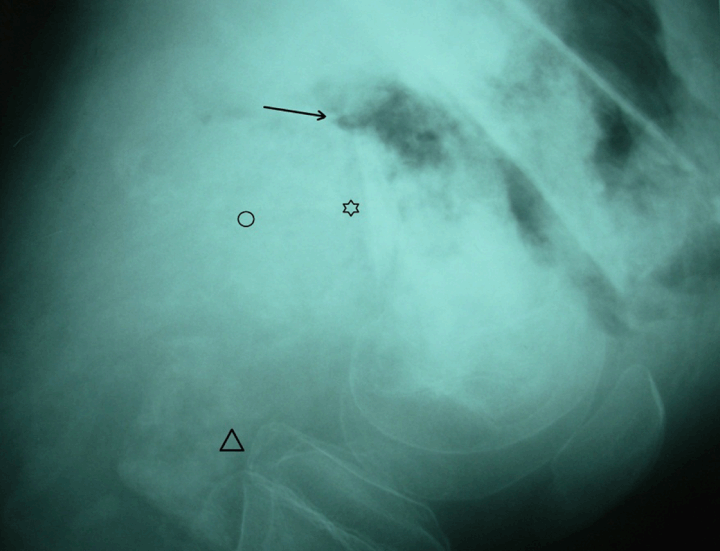

He had severe anemia with hemoglobin of 5 g/dL. The rest of routine laboratory tests were within normal levels. Radiography showed an expansive lytic lesion of the distal end of the femur with cortical destruction, focal periosteal reaction and a pathologic fracture. (Figure 1) It showed massive extension to adjacent soft tissue. Given the advanced stage of the disease, an amputation of the limb was performed.

Figure 1: Plain radiograph showing an expansive and ill-defined destructive tumor of distal femur. There was focal periosteal reaction (star), cortical destruction and pathologic fracture (arrow). Massive extension to adjacent soft tissue was observed (circle). Articular surface and tibia were not involved (triangle).

The diagnosis of telangiectatic osteosarcoma requires presence of a predominantly lytic destructive lesion of bone with no or minimal lesional sclerosis on radiographic imaging. [1] [4] Periosteal bone formation is absent or minimal and is referred to as onion skin. [1] [2] The tumor commonly shows extension into soft tissues. [1] [7] Imaging features alone would also be compatible with an aneurysmal bone cyst, Ewing sarcoma, Langerhans cell histiocytosis, fibrosarcoma and malignant fibrous histiocytoma. [8] The pathologic findings enable confident exclusion of these radiologic differential diagnosis. [4]